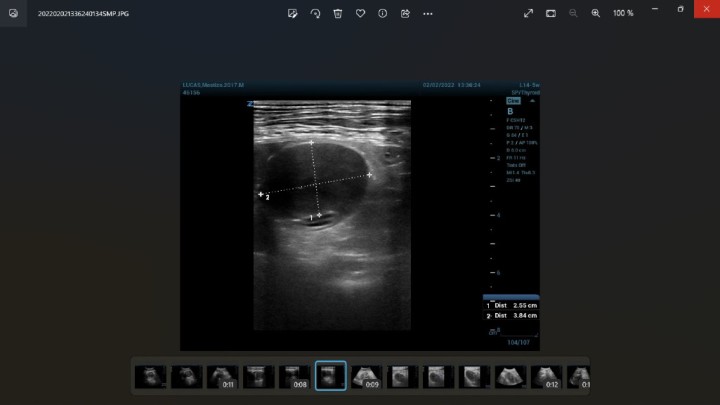

La ecografía abdominal (Resona7, Mindray, Shenzhen, China) evidenció una estructura de 4 cm de aspecto hipoecoico y bordes redondeados adherida a la capa serosa del duodeno, sin captación de señal Doppler. Los diagnósticos diferenciales compatibles con esta lesión son la neoplasia intestinal, el hematoma intramural intestinal o la presencia de un granuloma (Fig. 3 y Vídeo 1).

Figura 3

Imagen ecográfica de la lesión duodenal.

Vídeo 1. Vídeo ecográfico de la lesión duodenal. A través de este QR puedes visualizar la ecografía.